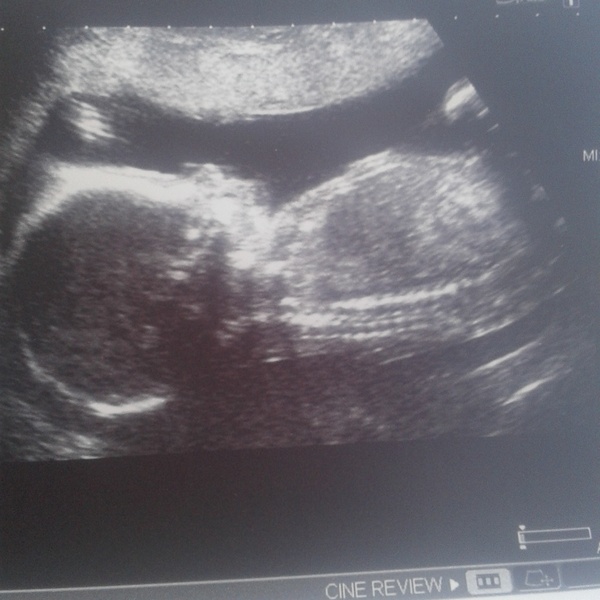

Out of 4 photos, this is the best. The others are blurry.

February 2016 - Boobs are growing, sickness is going, and some of us are finally showing!!